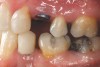

Figure 4a  Corticotomy SFOT. A 42-year-old male presented with a history of extraction orthodontic therapy (A). Incisors were too upright and had severe incisal wear. He was concerned about esthetics of the worn teeth and his insufficient lip support.

Figure 4a

Figure 4b  Progress photo and panorex 9 months after corticotomies were performed on Nos. 6 through 11 (B and C). Previous extraction sites were reopened orthodontically to improve function and fill lip support. Incisal edges were restored provisionally with composite resin. Note that despite the creation of adequate spaces to replace missing teeth, there is inadequate room for placement of dental implants because of severe tipping of all the anterior teeth. Osteotomy SFOT may have been a better choice because it would have allowed needed alveoloskeletal correction (without excessive tipping) instead of the primarily dentoalveolar correction common in corticotomy SFOT. Restorative dentist: Brad Jones, DDS.

Figure 4b